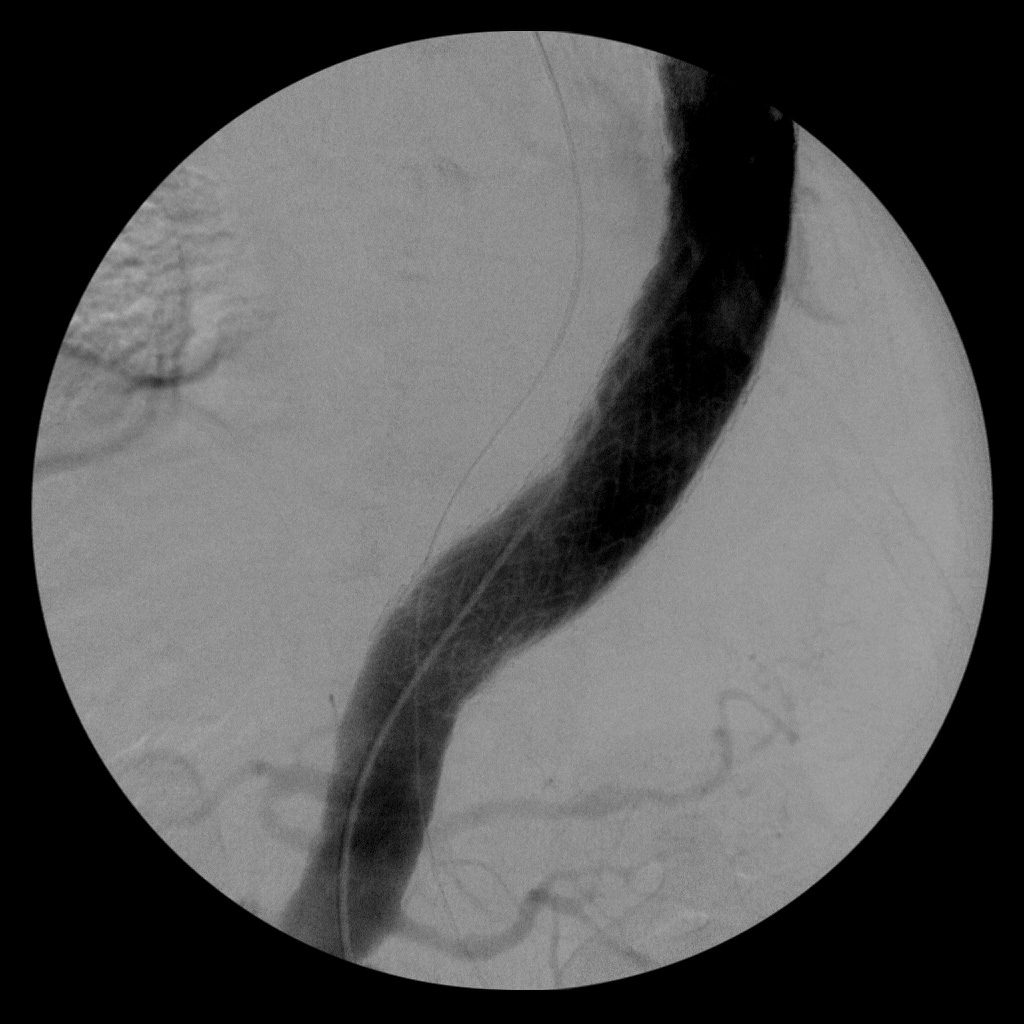

上圖:主動瘤破裂修補前(左)、後(右)

家屬在婦人耳邊聲聲呼喚,感覺她輕輕點頭回應,最後仍決定開刀。余榮敏主任緊急進行「主動脈瘤支架手術」,從病人鼠蹊部放入主動脈血管支架,把主動脈破裂的地方封住,手術時間前後近六個小時,微創傷口只有五公分,成功把婦人從接近百分之百死亡率的急重症搶救回來。更值得慶幸的是,後續住院觀察四十天,術後恢復比預期好,沒有嚴重後遺症,出院後還能出外聊天。